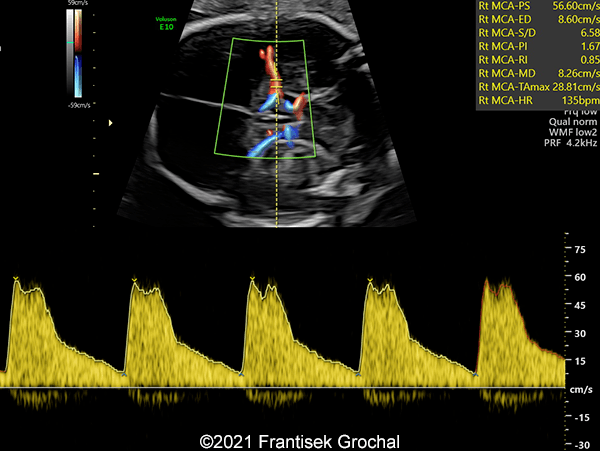

Case Report: A 24-year-old secundigravida, primipara presented to our office at 24 weeks and 6 days of her pregnancy due to a right-sided cranial parieto-occipital mass of the fetus. We obtained the following images.

Our ultrasound images at 24 weeks, 6 days show a highly vascularized, mostly solid mass measuring 58 x 45 x 34mm in the right-parieto-occipital subcutaneous region. Vascular supply of the lesion could be traced to the right vertebral artery. Repeat ultrasound exams done later in pregnancy demonstrated that the size of the mass remained stable with overall mass volume about 58 cm³.